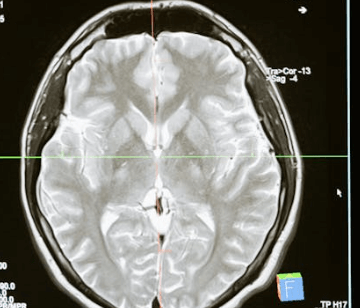

도파민은 우리의 행동, 감정, 인지, 학습, 기억, 보상, 욕구 등을 조절하는 뇌 내 신경전달물질 중 하나입니다. 뇌의 다양한 부위에서 생성되며, 도파민 수용체에 결합하여 신호를 전달합니다.

주된 역할은 즐거움이나 만족감을 느끼게 하고 동기를 부여하는 것입니다. 성취를 경험할 때 뇌에서 도파민이 분비되어 기분이 들뜹니다. 또한 기억, 기분, 수면, 학습, 집중, 신체 움직임 등을 조절합니다.